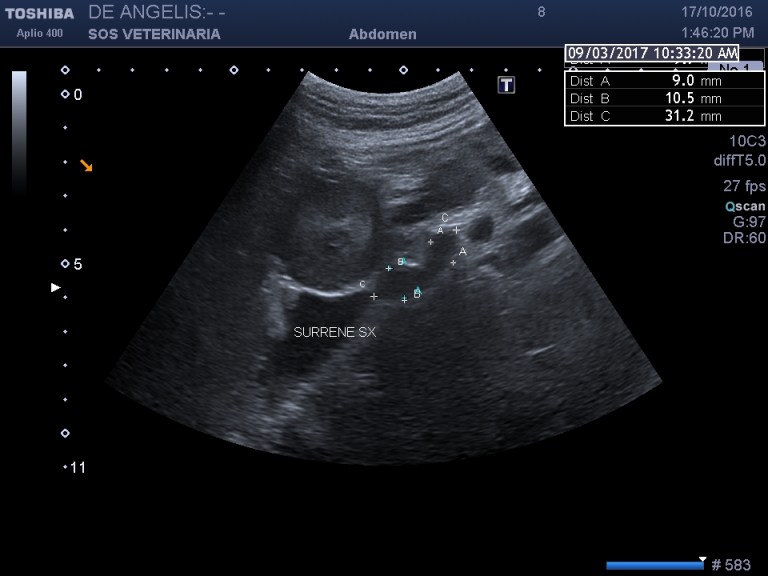

esame ecografico

evidente iperplasia della surrene sx le surrenali delle razze giganti sono molto piu’ difficili da visualizzare (sonda utilizzata da 6,5 mHz) e di dimensioni inferiori alle razze toy in proporzioni alla massa corporea,il limite di riferimento e’ impossibile stabilirlo per tutte le razze ci si affida al valore massimo di 7, 5 mm ai poli

nella destra asse lungo i valori superano di poco il riferimento

anche in asse corto si supera il valore di riferimento

evidente iperplasia ,morfologia conservata